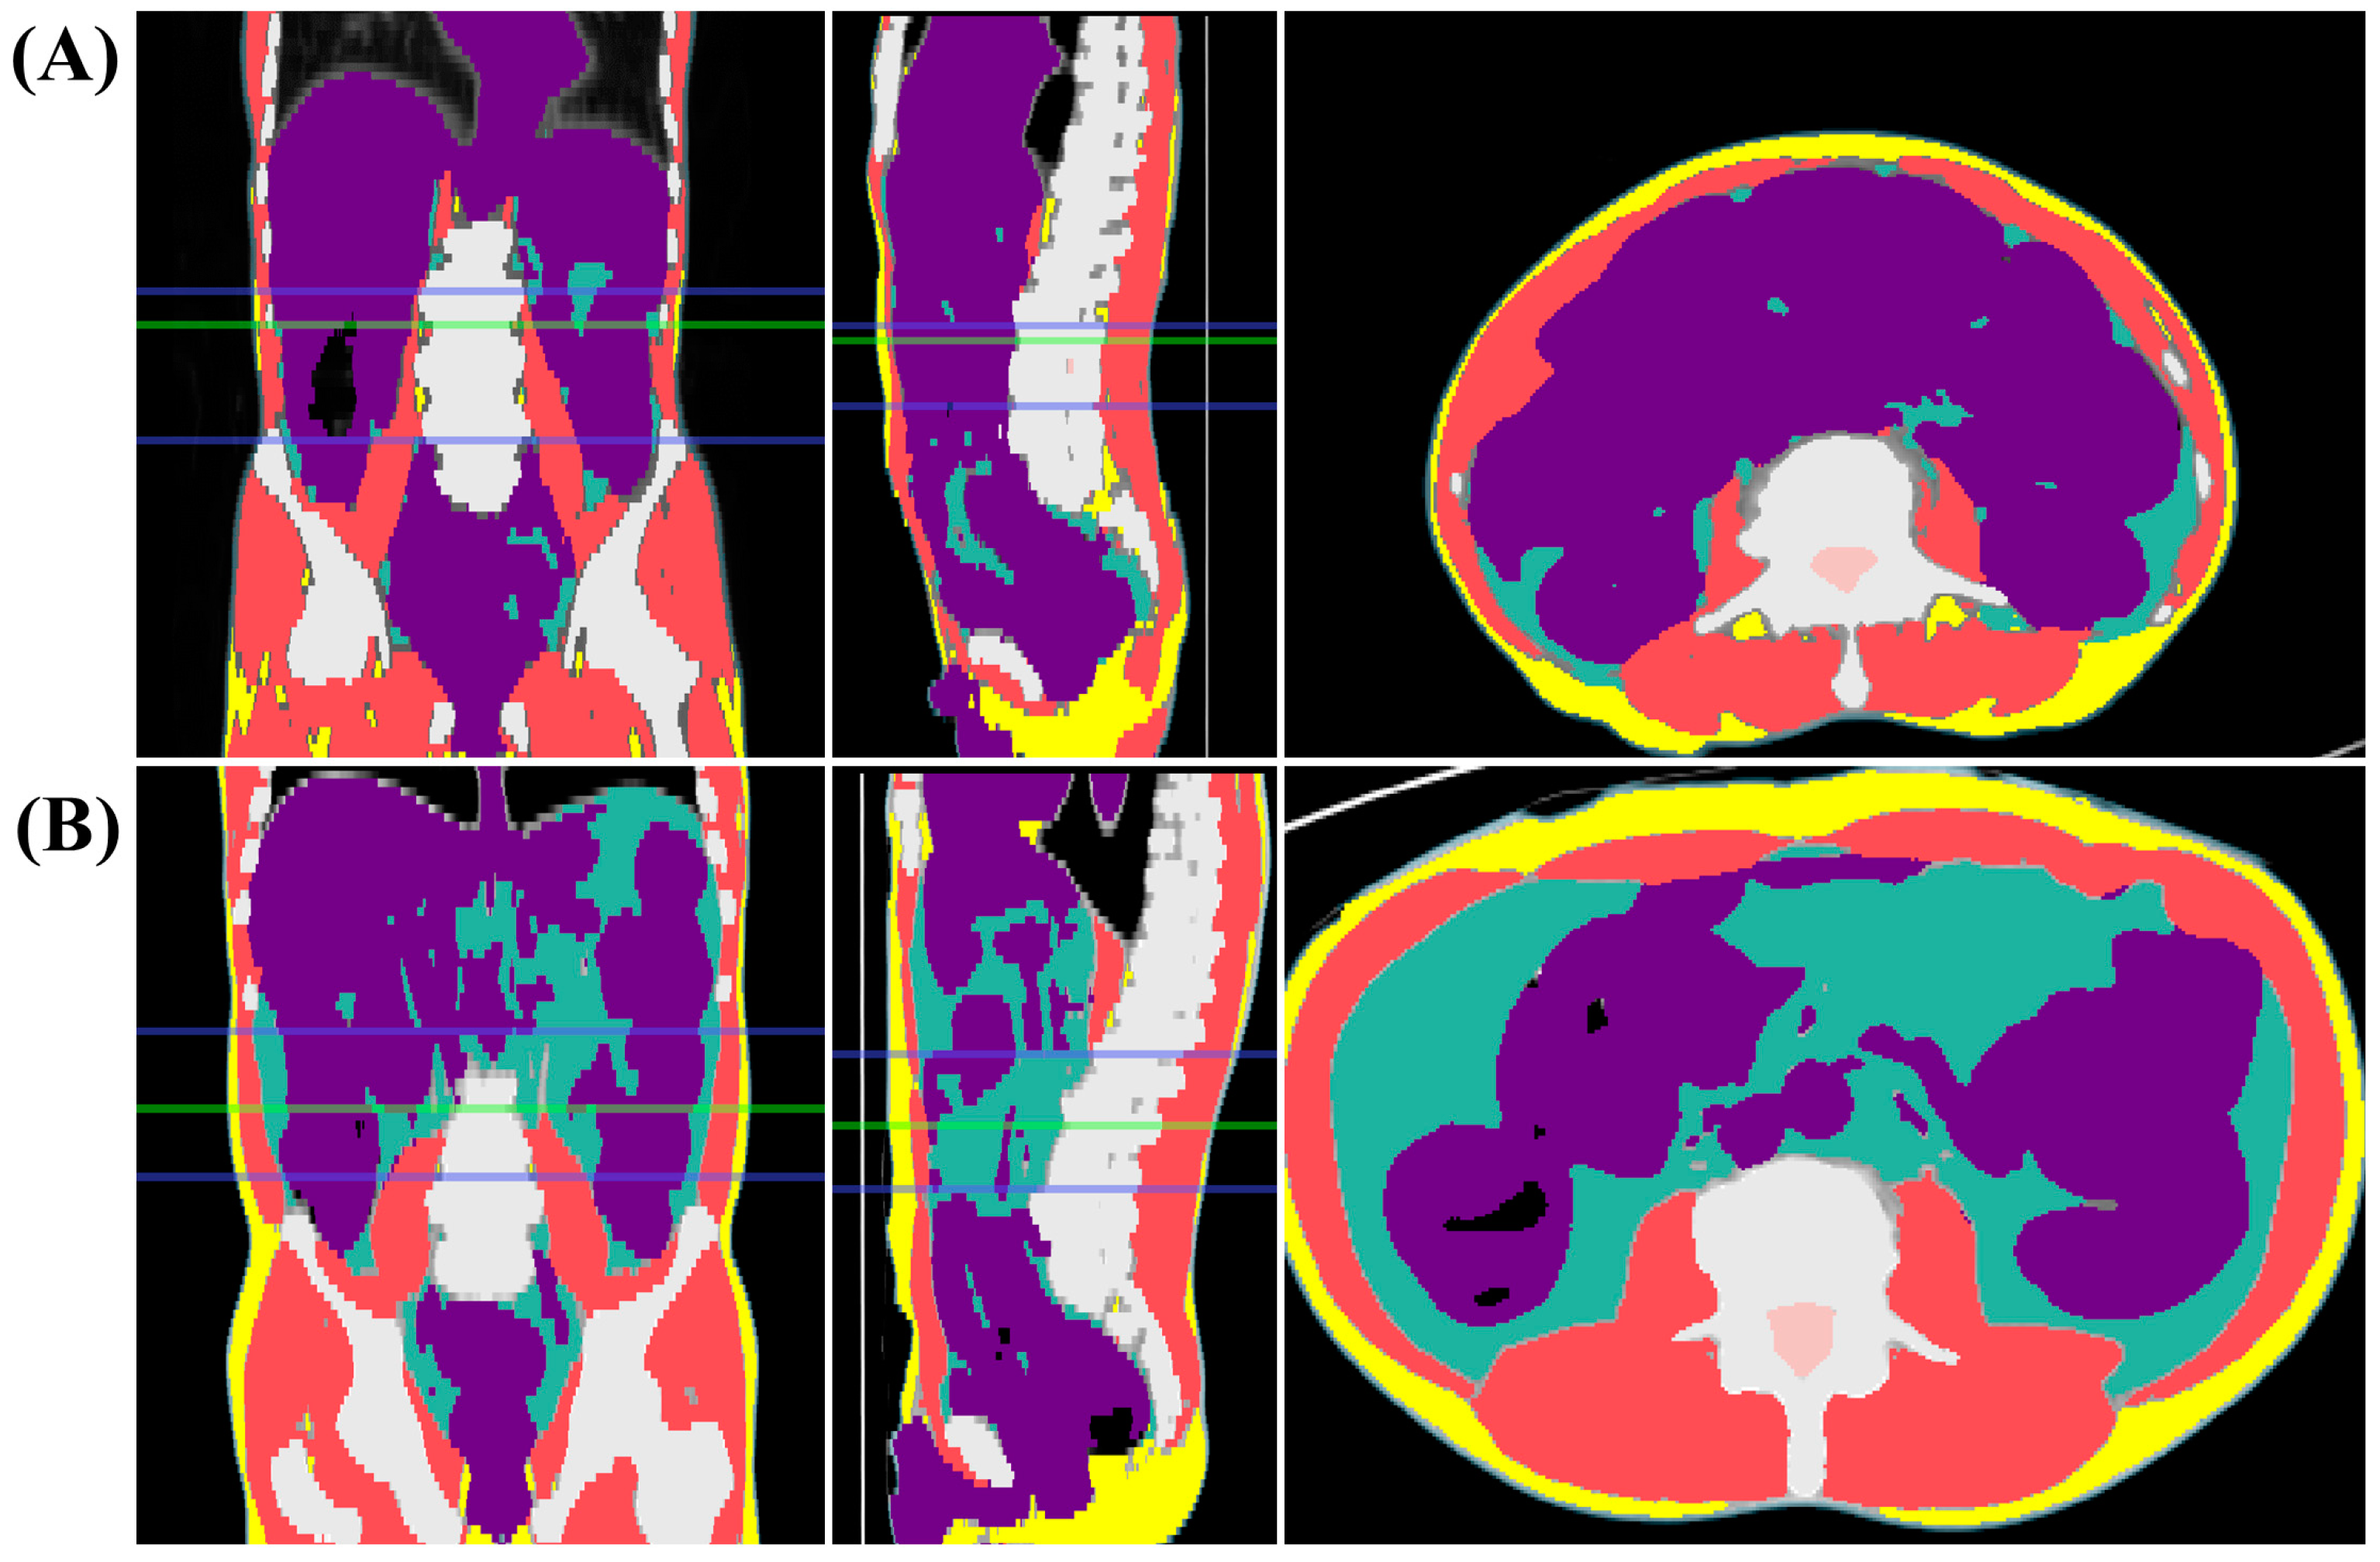

Figure 2.

Assessment of body composition through computed tomography (CT) images. (A) CT images of patients classified with volumetric sarcopenia. (B) CT images of patients classified with volumetric non-sarcopenia. The green line marks the L3 vertebral level, while the region between the two blue lines represents the abdominal waist. CT images display skeletal muscle (red), abdominal visceral fat (green), subcutaneous fat (yellow), and visceral organs (purple) within the defined area.